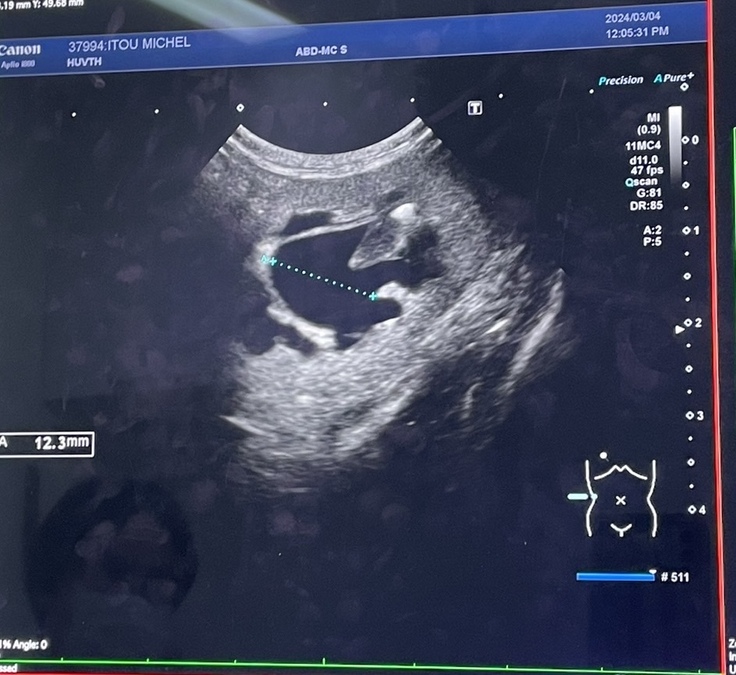

3/2時点、腎機能CREA 12.3mg/dl,BUN 130mg/dl と、数値は測定不能なレベル、いつなにがあってもわからない状態でした。

点滴入院を続けても、みしぇるの状態は悪化するばかりで数値の改善も見られず、大学病院(後B病院)を紹介していただき、3/4に受診しました。その結果、腎臓・尿管ともに結石が見られ、尿管は結石により詰まっており、腎臓も圧迫されている状態でした。